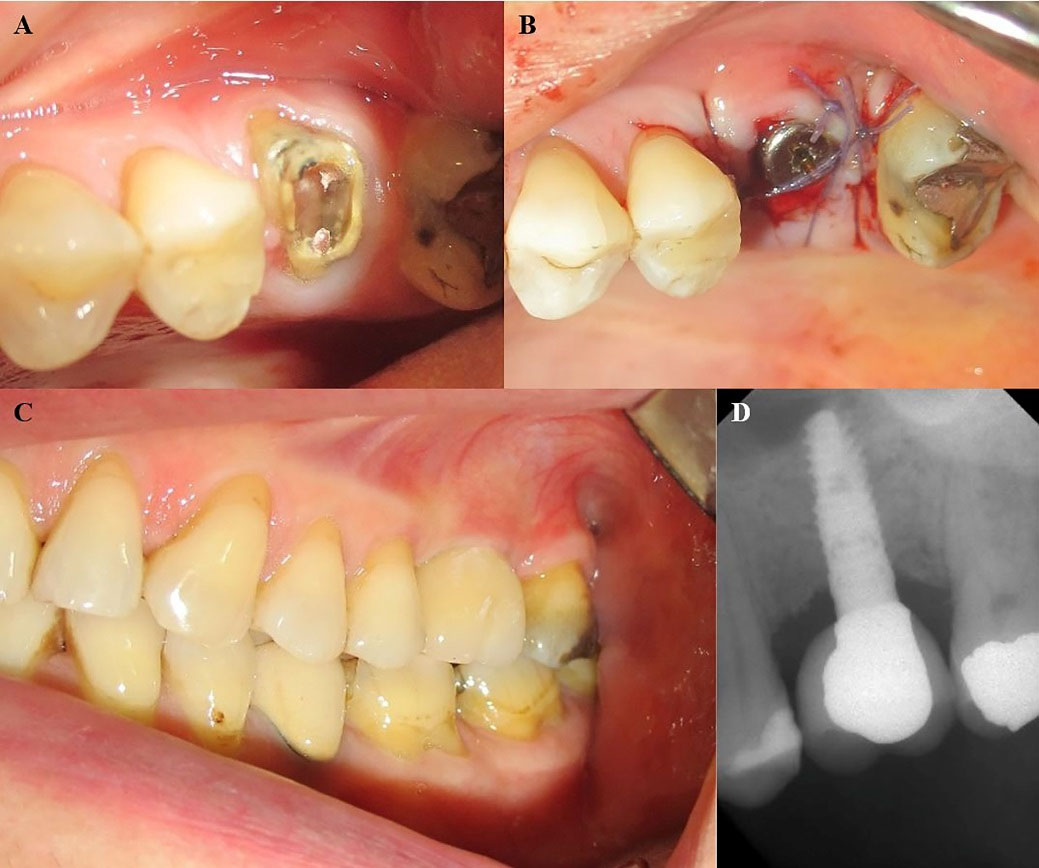

Figure 2.

(A) A 52-year-old female patient. Restoration of maxillary second premolar and first molar presented with food impaction and the patient was uncomfortable on chewing. (B) Photograph of the site after removal of the defective fixed partial denture. (C) Following the minimally invasive extraction of hopeless teeth, two implants (Xive system) were inserted. Sinus floor elevation by crestal approach was performed before the placement of the maxillary first molar implant. (D) Flaps were sutured by 4/0 Vicryl suture. (E) The collagen membrane is secured by a healing cap. (F) Clinical view of the maxillary right quadrant with implants in function. (G) Peri-apical radiograph of inserted implants after 62 months.